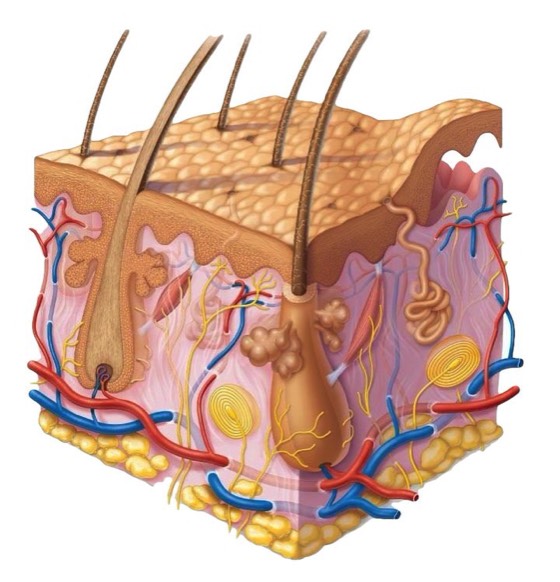

SISTEM INTEGUMENTARI

KULIT adalah organ yang terbesar pada tubuh manusia yang berperanan antara lain menjadi batas pelindung organ-organ dalaman dari terdedah pada mikro organisma dari persekitaran luar.

Kulit juga merupakan satu agen ‘sensori’ dimana apa jua yang berlaku keatasnya akan dapat dirasakan melaui jaringan sensori dan saraf yang memberi isyarat kepada otak untuk tindakan selanjutnya.

Apakah bicara ALQuran tentang kulit? Firman Allah pada ayat 56 surah An-Nisa’ memberitahu bahawa reseptor deria rasa sakit pastinya terdapat pada kulit yang menjurus kepada cabang anatomi yang disebut sistem Integumentari.

Pada ayat 23 surah Az-Zumar dikhabarkan bahawa adanya semacam deria rasa pada kulit ketika wujudnya rasa ketakutan atau keresahan sepertimana kita kadangkala menyebut “berdiri bulu roma”. Kadangkala kita merasakan seperti ada rasa tusukan pada kulit dan juga rasa seperti ada semut bergerak dipermukaan kulit. Demikianlah beberapa sifat kulit yang bertukar mengikut kewujudan sensori yang menyentuh perasaan atau saraf. Sentuhan pada kulit juga dapat merangsang saraf selari dengan cara sentuhan dilakukan.

Kulit juga dikhabarkan mempunyai kuasa menyimpan memori data yang akan dikeluarkan kembali pada Hari Kiamat nanti seperti mana difirmankan pada ayat 19-21 surah Fussilat.

Tiga potong ayat ini memberi bayangan bahawa kulit yang menjadi pelindung tubuh kita akan menjadi saksi diHari Kiamat nanti. Sekiranya kita mendalami ilmu DNA dan kaitannya pada kulit kita akan sedikit sebanyak mendapat pencerahan.

Pada pertengahan tahun 2007 majalah “Neuroscience” telah menerbitkan satu kajian saitifik terhadap kulit dimana mereka mendapati wujudnya sel yang mengandungi molekul CaMKII yang bertanggungjawab dalam menyimpan ‘memori’.